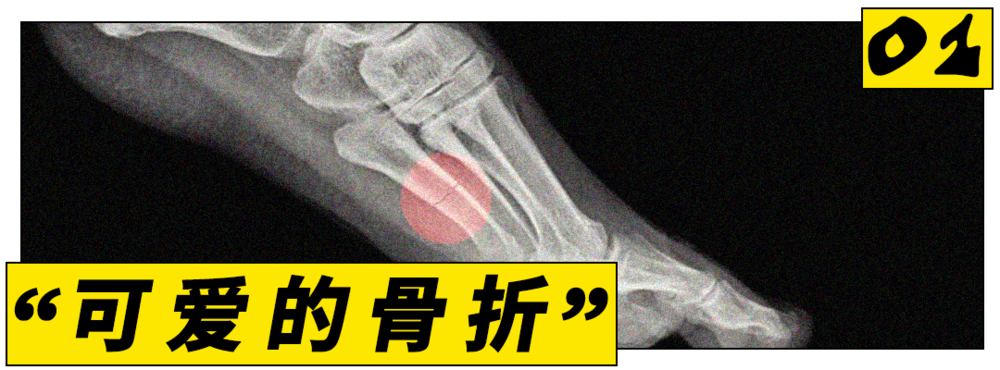

21世紀(jì),跑步的火爆程度早已超出了一項運動本身。要問2026年跑步圈最火的話題是什么,應(yīng)力性骨折一定榜上有名。

用一句話概括的話,它是由長期運動所引發(fā)的微小骨裂,也或許是今年最流行的傷痛。根據(jù)Google搜索趨勢,今年關(guān)于應(yīng)力性骨折的關(guān)注度已創(chuàng)下了自2004年以來的新高。

今年年初,這些健壯的女性卻集體出現(xiàn)了不同程度的應(yīng)力性骨折癥狀。視頻上看,她們需要在腿上一直戴著固定護具,以防二次受傷。

骨折不是稀事,但奇怪的點在于,過去會患上應(yīng)力性骨折的往往是專業(yè)的跑步選手。據(jù)統(tǒng)計,大約40%的運動員在一輩子里至少會得一次應(yīng)力性骨折。

一篇學(xué)術(shù)報告也指出,這種骨折常見于精英運動員和軍事訓(xùn)練人群。這些人的下肢會長期承受重復(fù)性沖擊負(fù)荷,一般人不會受這樣的傷。